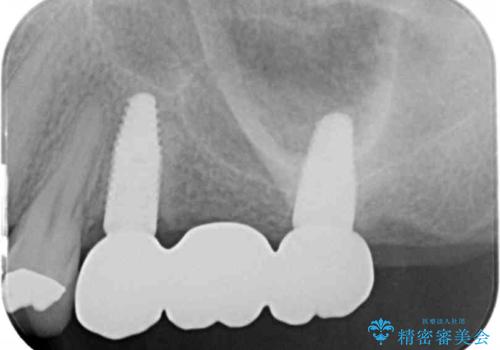

[根管治療・セラミッククラウン] 前歯の痛み・見た目を改善したい

- 前歯の痛み、不自然さを解消したいと来院されました。

X線写真検査より感染根管による根尖性歯周炎、レジン前装冠の欠け、コンポジットレジン充填によるツギハギになってしまった歯が認められました。

それぞれの問題点に対し、感染根管治療・ジルコニアクラウンの製作を行い感染の除去・審美性の回復を計画します。

感染根管治療を行ったことで痛みはなくなり、ジルコニアクラウンによる再補綴を行ったことで自然な透明感を再現した歯になり審美性を回復することができました。